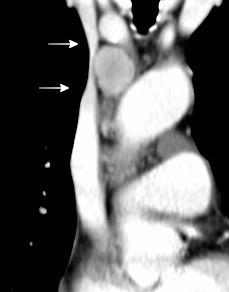

La línea de la arteria subclavia izquierda (ASI) es cóncava en el normal

ASI NORMAL

Frecuentes

Elongación de troncos

Aneurismas de ASI/ACI

Anomalías vasculares

Bocio/ Ca. de tiroides

Ganglios/ Grasa

Menos frecuentes

Tumores traqueales

Masas esofágicas

Tumor neurogénico

Tumores de Pancoast

Aneurisma de ASI

Aneurismas de TSA

74 pacientes

Degenerativos…63%

Iatrogénicos……24%

Trauma…………..8%

Genético………..3%

Micótico…………1%

ASD…50%. 2/3 lado dcho.

Carótida común 36%%

Carótida interna ..10%

TBD…………………..3%

Vertebral……………1%

Cury M et al.Supra-aortic vessels aneurysms: diagnosis andprompt intervention. J Vasc Surg. 2009